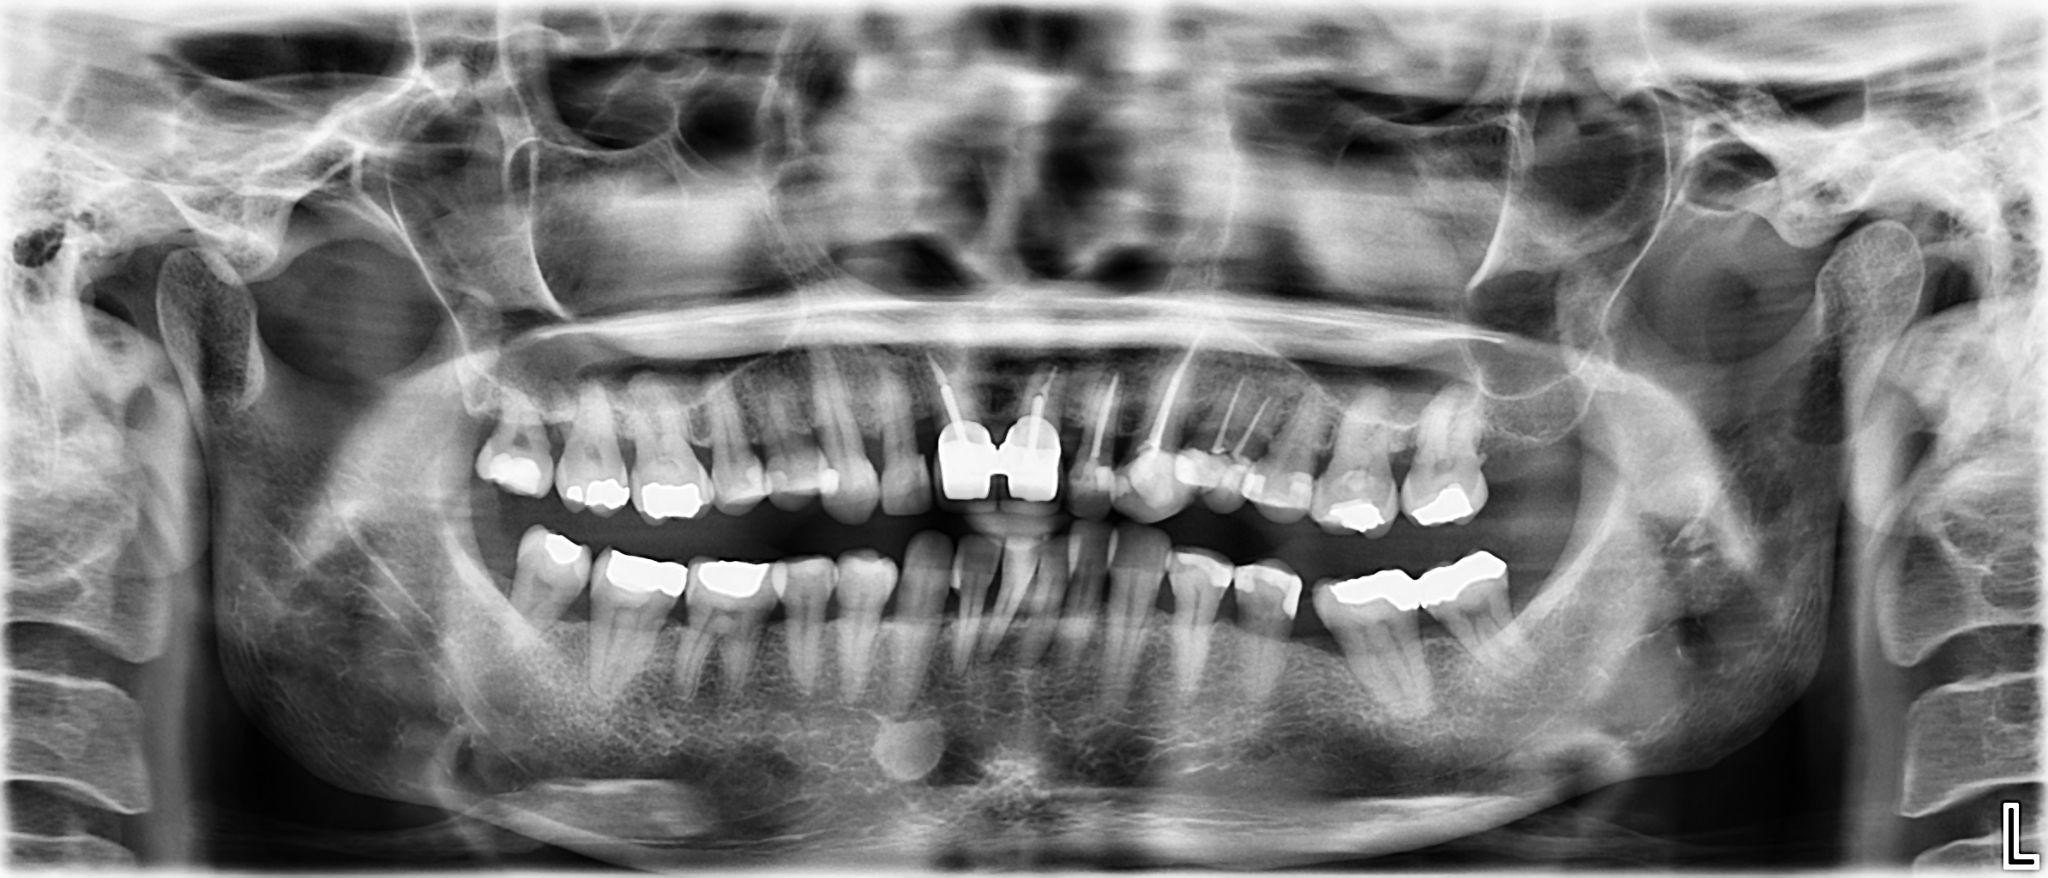

6. What option cannot be selected for this panoramic X ray?

7 / 23